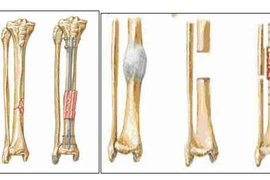

(khoahocdoisong.vn) - Bị tai nạn giao thông mất một đoạn xương và qua nhiều đợt mổ không thành công, có nguy cơ phải cắt chân. Nhưng các bác sĩ Bệnh Viện Hoàn Mỹ Sài Gòn đã phẫu thuật kết hợp xương thành công giúp người bệnh có được niềm vui trong cuộc sống.